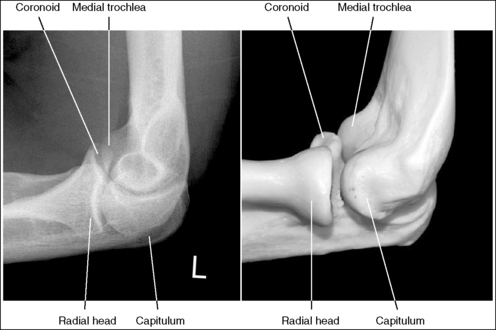

The elbow is in a lateral projection. The distal humerus demonstrates three concentric arcs, which are formed by the trochlear sulcus, capitulum, and medial trochlea. The elbow joint space is open, and the radial head is superimposed over the coronoid process.

• A lateral elbow projection is obtained when the humeral epicondyles are positioned directly on top of each other, placing an imaginary line drawn between them perpendicular to the IR. To obtain this humeral epicondyle positioning, place the humerus parallel with the IR and elevate the distal forearm until the palpable medial and lateral epicondyles are superimposed (Figure 4-78). This positioning aligns the trochlear sulcus, capitulum, and medial trochlea into three concentric (having the same center) arcs (Figure 4-79). The trochlear sulcus is the small center arc. It moves very little when a positional change is made and works like a pivoting point between the capitulum and medial aspect of the trochlea. The largest of the arcs is the medial aspect of the trochlea. It is demonstrated very close to and slightly superimposed on the curve of the trochlear notch. The intermediate-sized arc is the capitulum. When these three arcs are in accurate alignment, the elbow joint is visualized as an open space and the anterior and proximal surfaces of the radial head and coronoid process are aligned.

Figure 4-79 AP (left) and lateral (right) images showing anatomy of the distal humerus. (From Martensen K III: The elbow, In-Service Reviews in Radiologic Technology, 14[11], 1992.)